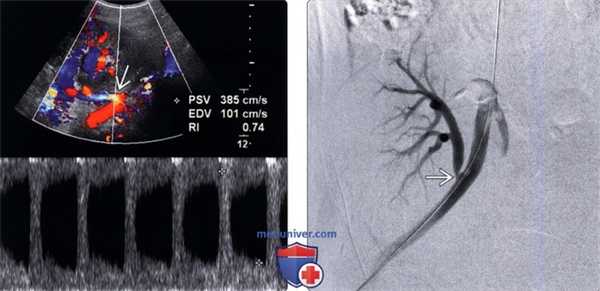

(Левый) Допплерографический срез через анастомоз почечной артерии у пациента с острым повреждением почки через год после трансплантации от умершего донора. В анастомозе визуализируется цветовой дефект наложения с пиковыми скоростями, превышающими 385 см/с.

(Правый) При цифровой субтракционной ангиографии у этого же пациента подтвержден выраженный стеноз (>90%) в области анастомоза S3, скорректированный путем ангиопластики.